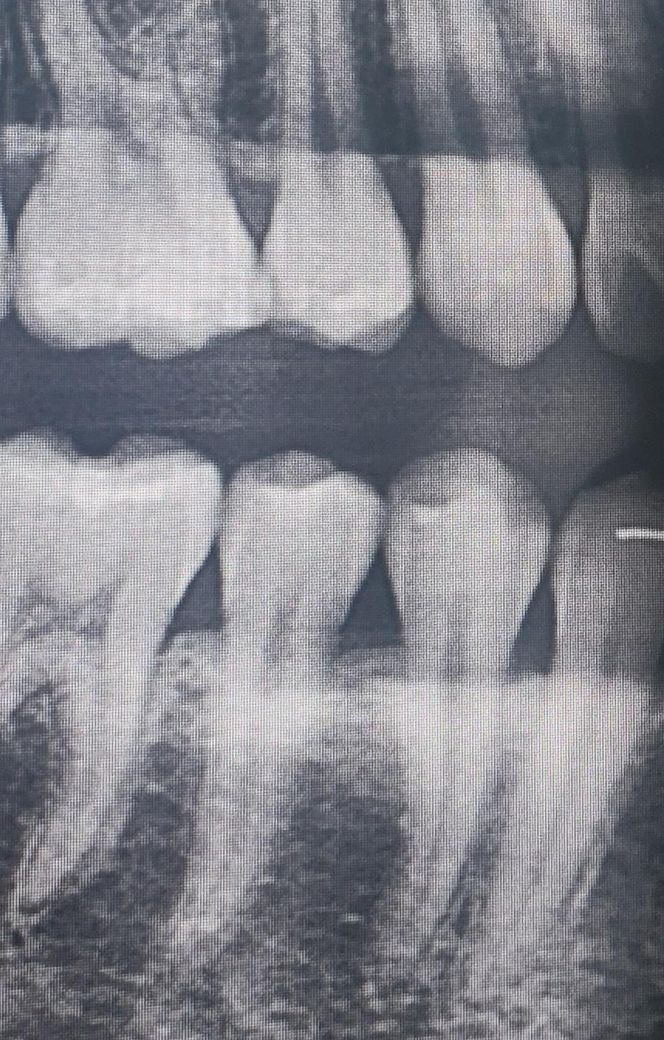

제 치아 풍치인가요? 확인해주세요ㅠㅠ

제 치아 풍치인가요? 요즘 자주 잇몸이 부어서요

특히 체크 표시된 소구치가 가장 신경쓰입니다.

엑스레이 사진 첨부합니다.

풍치 등으로 인해서 치아가 흔들리기 위해서는 치조골이 많이 손상이 되어야 합니다. 사진으로만 봤을 경우에는 치조골이 많이 손상된거로 보이는 않습니다. 치조골을 건강하게 유지하기 위해서는 치아 주변에 있는 이물질을 양치질과 치실로 꼼꼼하게 제거를 해줘야 합니다.

엑스레이 상으로는 잇몸뼈가 크게 문제가 잇어 보이진 않습니다. 양치가 잘안되는거 같으니 양치를 하실때 조금더 꼼꼼히 하시는게 좋을것같습니다.

아직까지는 풍치라고 할 정도로 치조골이 나쁜 편은 아닙니다. 다만 계속해서 잇몸이 붓는다면 붓는 원인을 알고 해당 부위를 지속적으로 관리해주어야 더 큰 잇몸 질환으로 이어지는 것을 막을 수 있습니다. 따라서 왜 해당 부분이 붓는지 원인에 대한 평가를 받아보시길 바랍니다.

잇몸이 붓는다고 풍치라고 하지는 않으며 아직 심하게 진행된 것으로 보이진 않습니다.